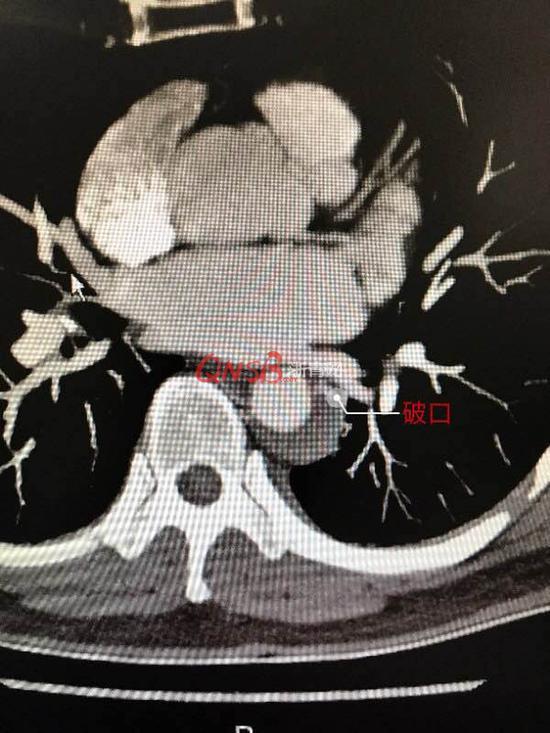

CT片顯示主動脈內膜破裂口

醫生解釋說,主動脈有三層血管壁,主動脈內膜破了,血液從血管腔經破口流入血管中間層,血管壁形成血腫(血寶),也就是醫學上稱之為夾層。破口較小或者壓力低,通過控制血壓、心率等,使內膜的破口愈合;若主動脈夾層壁間血腫繼續增大,發生主動脈夾層破口,未及時外科手術治療,那將危及生命。醫生分析,鄭女士瑜伽有拉伸動作,很可能主動脈經拉伸導致滋養動脈或者內膜破了。